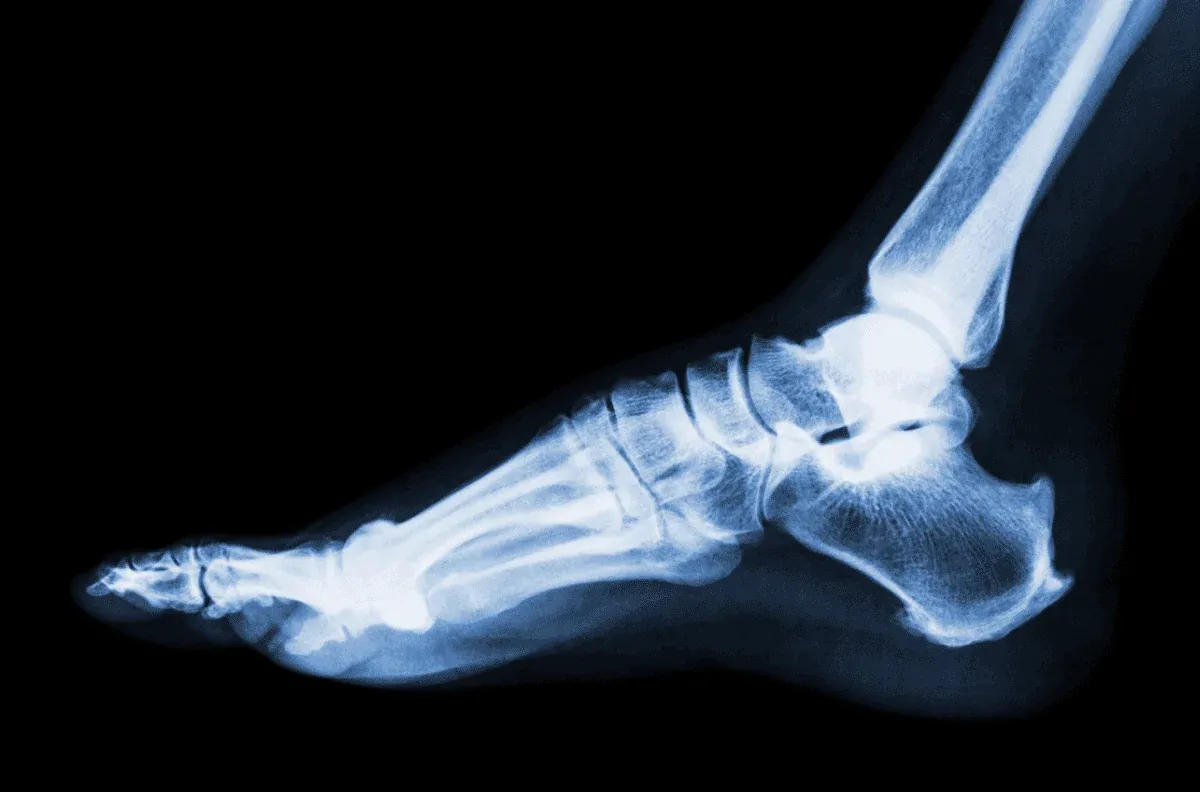

Skręcenie kostki II stopnia to uraz, który często występuje podczas aktywności fizycznej. Czas gojenia wynosi zazwyczaj od 4 do 6 tygodni, ale może się różnić w zależności od wielu czynników. Właściwe leczenie i rehabilitacja są kluczowe dla szybkiego powrotu do zdrowia. W przypadku skręcenia kostki II stopnia dochodzi do częściowego rozerwania więzadeł, co powoduje ból i ograniczenie ruchomości stawu. Właściwe podejście do leczenia, w tym odpoczynek i rehabilitacja, może znacząco wpłynąć na czas powrotu do pełnej sprawności.Czas gojenia – co warto wiedzieć o 4-6 tygodniach?